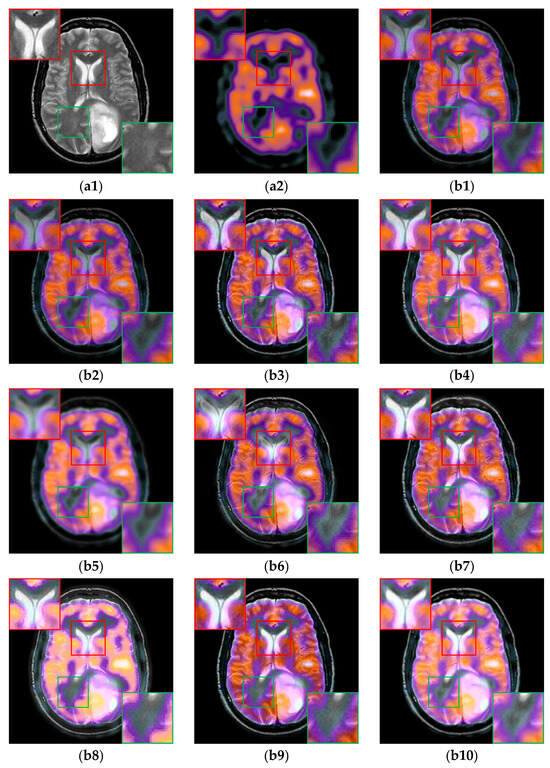

The fusion results of SPECT-CT/MR image pairs are shown in Figure 7. As indicated by the red boxes, U2Fusion, DenseFuse and RFN-Nest cannot maintain the sharpness of details from MR image, and IFCNN, PAPCNN and TIF produce the unwanted ringing artifacts. As shown by the green boxes, NestFuse, ReLP and CDDFuse reduce the contrast of the details from the SPECT image. By comparison, CIRF can not only avoid undesirable artifacts but also preserve the important details from MR and SPECT images effectively. These results also indicate that CIRF has a good generalization ability when applied to different datasets.

Figure 7. The results of all algorithms on the SPECT-CT/MR image pairs from Atlas dataset. (a1) Source CT/MR image; (a2) Source SPECT image; (b1) U2Fusion; (b2) DenseFuse; (b3) IFCNN; (b4) NestFuse; (b5) RFN-Nest; (b6) PAPCNN; (b7) ReLP; (b8) TIF; (b9) CDDFuse; (b10) CIRF.